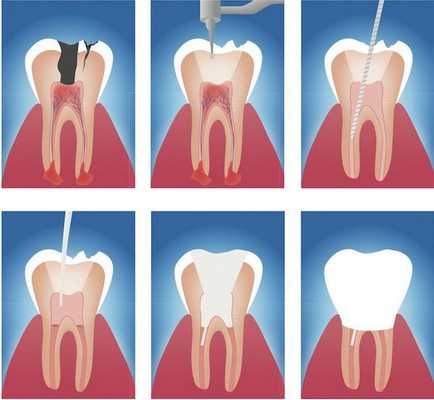

Этапы эндодонтического лечения:

- адекватное обезболивание;

- изоляция зуба или нескольких зубов, в которых будут проводится манипуляции, от полости рта;

- создание эндодонтического доступа (иссечение твёрдых тканей зуба или пломбировочного материала, закрывающих доступ в систему корневого канала;

- прохождение и определение длинны корневого канала (это длинна от устья до верхушки корня);

- создание корневого канала определённого диаметра и формы;

- введение в корневой канал лекарственных препаратов;

- пломбирование корневого канала;

- восстановление анатомии и функции зуба с помощью пломбировочного материала или ортопедической конструкции.

– Проводниковая анестезия Sol.Articaini 1:100000 1,7 ml

– Удаление прежней пломбы, препарирование кариозной полости

– Создание эндодонтического доступа, раскрыта полость зуба

– Ампутация коронковой и экстирпация корневой пульпы (рис. 2).

– Определена рабочая длина корневых каналов.

– Инструментальная обработка корневых каналов в сочетании с RC-prep.

– Медикаментозная обработка корневых каналов раствором «Белодез», высушивание.

– Пломбирование корневых каналов пастой «Endomethasone» с гуттаперчивыми штифтами методом латеральной конденсации. Коагуляция гуттаперчивых штифтов. Постановка временной пломбы

– Rg-контроль пломбирования корневых каналов.

– Снятие временной пломбы

– Обезжиривание кариозной полости, на устья корневых каналов изолирующая прокладка «Глассин Бейз», анатомическая форма зуба восстановлена «Charisma» химического отверждения. Шлифовка, полировка пломбы (рис. 3).